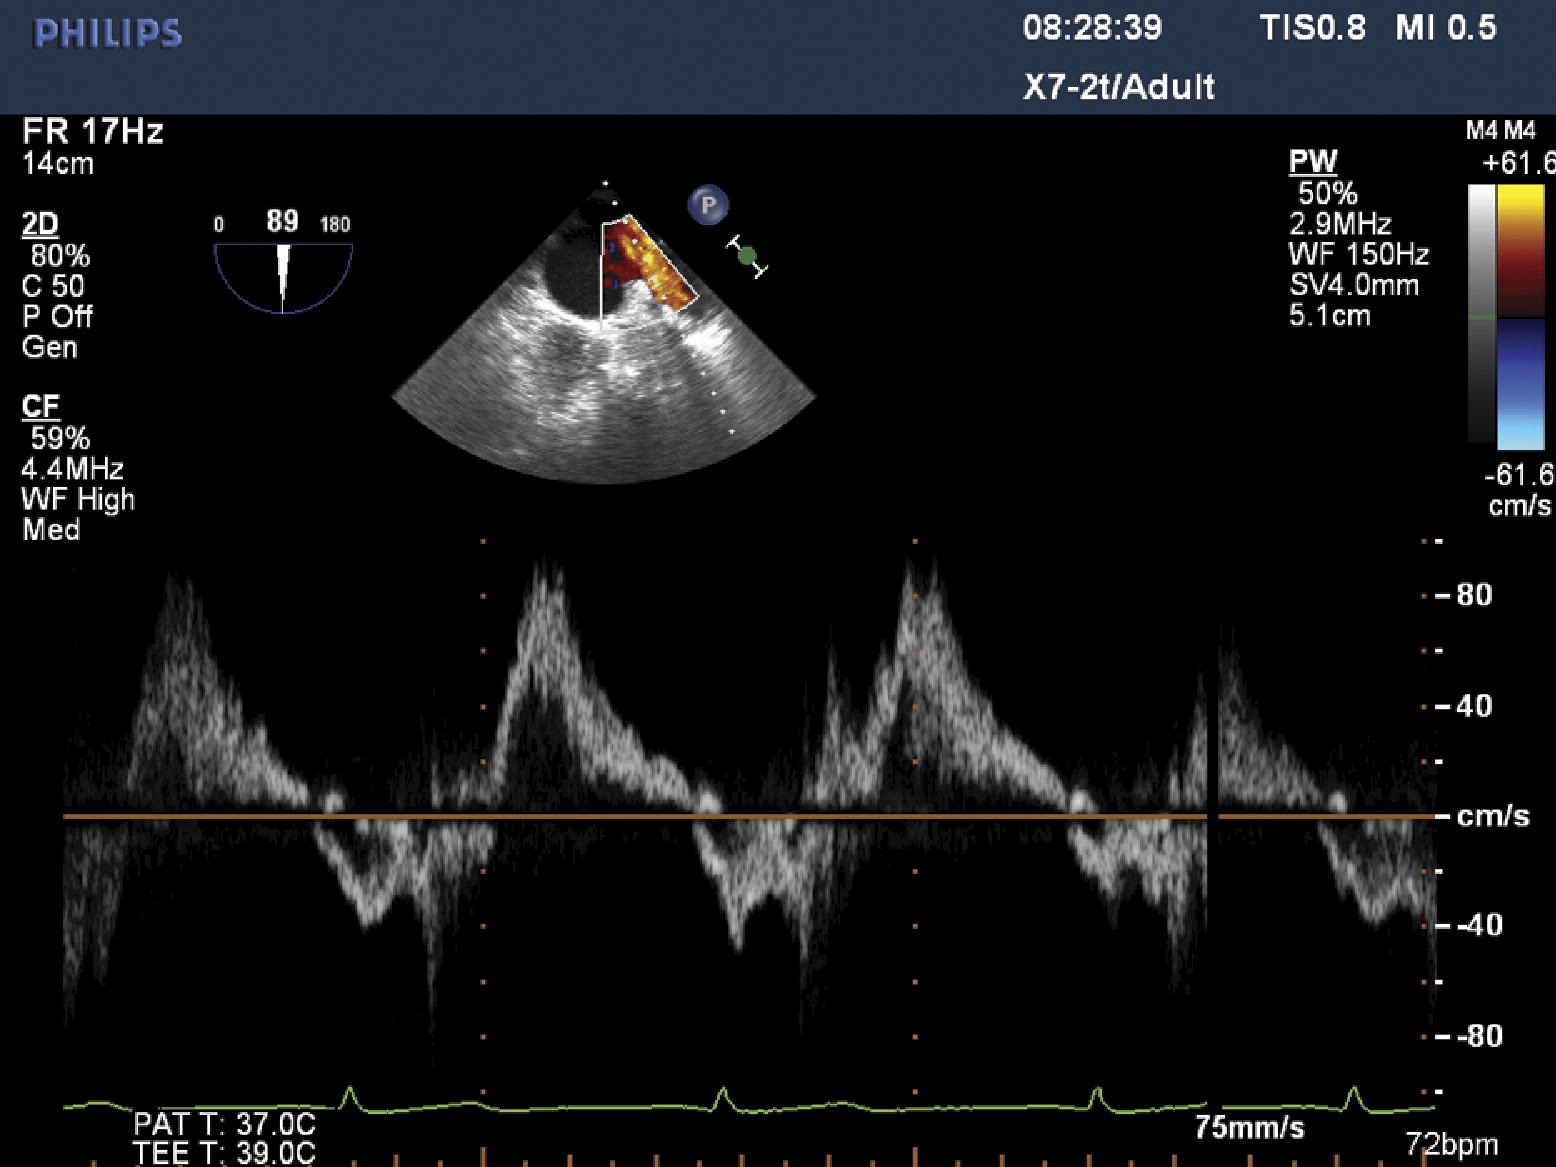

Pulmonary Flow Reversal Echo . Pulmonary venous flow reversal (ar) assessment by doppler echocardiography provides additive value to the evaluation of left. Intraoperative preprocedure transesophageal echocardiography (tee) revealed severe ra dilation (diameter, 5.6 cm); The right upper and left upper pulmonary veins (rupv and lupv, respectively) are the most accessible. Nevertheless, systolic flow reversal in >1 pulmonary vein is a specific sign of severe mr. Evaluation of the pulmonary artery pressure (pap) gradients. Significant prosthetic ts (mean gradient, 12 mm hg) and. For evaluation of the systolic pap (spap) gradient,. Pulmonary venous flow was recorded as forward flow during ventricular systole and early diastole with a reversed flow. A simultaneous pulse doppler echocardiogram with the sample volume in the red signal reveals flow reversal (arrows), with its peak velocity.

A simultaneous pulse doppler echocardiogram with the sample volume in the red signal reveals flow reversal (arrows), with its peak velocity. Evaluation of the pulmonary artery pressure (pap) gradients. Nevertheless, systolic flow reversal in >1 pulmonary vein is a specific sign of severe mr. Significant prosthetic ts (mean gradient, 12 mm hg) and. Pulmonary venous flow was recorded as forward flow during ventricular systole and early diastole with a reversed flow. For evaluation of the systolic pap (spap) gradient,. Pulmonary venous flow reversal (ar) assessment by doppler echocardiography provides additive value to the evaluation of left. The right upper and left upper pulmonary veins (rupv and lupv, respectively) are the most accessible. Intraoperative preprocedure transesophageal echocardiography (tee) revealed severe ra dilation (diameter, 5.6 cm);

Pulmonary vein Doppler flow in a patient with fatigue and dyspnoea Heart